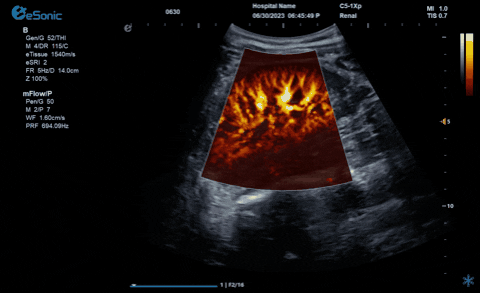

银河官网医疗的eHertz系列彩色多谱超声诊断系统凭借强大的RawVision?原数精准平台和SDBeam?软波声束合成技术推出专属的mFlow ?超微血流显像技术,该项技术可专用于极低速血流成像。彩色多普勒血流(CDFI)检查时,通常会将滤波器的频率设置为大约50hz,并随时调整标尺和增益,以便在背景噪声发生前显示小血管......